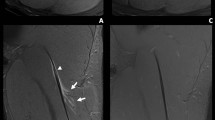

Considering the ROIs drawn on the initial (visit 1) images, incorporating the whole of the initial tear, T2 values were significantly lower at visit 2 in the tear site, haematoma and oedema ROIs (Fig. 2, Table 2). MD, λ2 and λ3 were significantly reduced after healing in the tear site and oedema, and FA was increased. There was no significant change in λ1 and there were no significant longitudinal differences in normal muscle for any of the measures.

Visit 2 ROIs

Considering the ROIs drawn on the visit 2 images within the tear site, there was still a significant reduction in T2, MD and λ3, and an increase in FA, with healing but differences in λ2 were no longer significant (Fig. 3, Table 3).